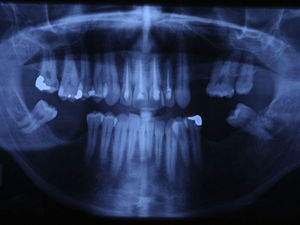

Case reportA case of a nasopalatine duct cyst in a 45-year-old male is presented (Fig. 1). The patient was referred, reporting a pressure over the anterior maxilla. There were no other symptoms and no recent history of pain. Clinical examination revealed a palatal expansion on the anterior hard palate (Fig. 2). There was no previous history of trauma. The patient was asked to take a computerized axial tomography which showed a well-defined radiolucency in the anterior maxilla in the region of incisive canal (Fig. 3). Loss of cortical bone was seen along the palatal aspect of the lesion in the sagittal sections (Fig. 4). Also resorption of nasal cavity floor bone could be seen in those sections. The cyst was enucleated under general anaesthesia. A palatal mucoperiosteal flap was raised and following bone removal, the friable, haemorrhagic cyst lining was curetted and sent for histological examination fixed in 10% neutral formalin (Figs. 5 and 6). After cyst removal it could be seen in the depth of surgical loca a small communication with the nasal cavity. Gross examination revealed a whitish, soft consistency fragment measuring 2.2cm×1.5cm×0.4cm (Fig. 7). Microscopic examination revealed fibrous wall lined by thin stratified squamous epithelium without inflammatory infiltrate and with some clear cells of ciliated appearance, which confirms the diagnosis of nasopalatine duct cyst (Fig. 8). The patient showed no clinical or radiographic signs of recurrence one year after surgical excision (Fig. 9).

In occlusal radiographs, they are seen as well defined round or oval radiolucencies in the midline, although some lesions can appear heart-shaped, because the nasal spine is superimposed on the radiolucent area.10,26

As the incisive canal and foramen may normally vary greatly in size, the clinician may have some difficulty in distinguishing between a large incisive foramen and a small asymptomatic incisive canal cyst on the basis of radiographic evidence alone. Some clinicians follow the thumb rule which says that radiolucencies of the incisive canal measuring less than 0.6cm in diameter should not be considered cystic in the absence of other symptoms.7,10 A radicular cyst or a granuloma associated with the central incisor should also be considered in differential diagnosis as these entities may be similar in appearance to an asymmetric NPDC. The presence or absence of the lamina dura and enlargement of the periodontal ligament space around the apex of the central incisor indicates an inflammatory lesion. NPDC and radicular cysts can also be differentiated by vitality tests once vitality of nearby teeth of a NPDC should not be affected. However, it is not uncommon to see evidence of endodontic therapy because the nasopalatine duct cyst was previously clinically misdiagnosed as a periapical cyst or granuloma.6,12 This is probably the reason why, in our case, the four maxillary incisive had yet root channel therapy when patient was referred to us. A residual cyst, a keratocyst and even central bone tumours can be confused with NPDC.18